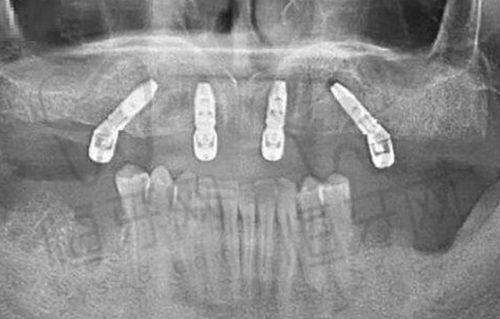

种植牙价格

韩国登腾:2980-7000元/颗

美国皓圣:3500-9800元/颗

瑞士ITI:6200-13000元/颗

瑞典诺贝尔:6500-15800元/颗